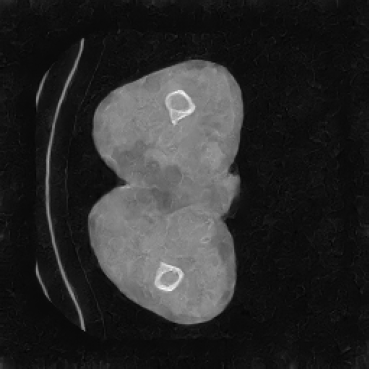

In our approach, we employ a compression factor of 4 to encode 3D medical images into the latent space. This level of compression reduces the spatial resolution of the original image (e.g., from 256×256 to 64×64 per slice), while still preserving the essential anatomical structures and semantic content. The latent representation at this scale offers a favorable trade-off between dimensionality reduction and semantic fidelity. Specifically, although fine-grained textures are simplified, key structural patterns (e.g., organ boundaries, lesion shapes) remain visually distinguishable and semantically coherent. As the compression rate increases, the latent representations become progressively more abstract. With lower compression (e.g., 2× or 4×), the latent features preserve key anatomical structures and spatial layouts, making them beneficial for our semantic image synthesis task in latent space, as the model can operate on compressed representations that retain sufficient semantic information without being overwhelmed by high-frequency noise. In contrast, higher compression rates (e.g., 8× or above) lead to a loss of fine-grained details and reduced semantic fidelity. The choice of a 4× compression thus ensures that the latent features are compact and meaningful, facilitating effective conditional generation while significantly reducing computational overhead. We therefore adopt a 4× compression as a compromise between computational efficiency and semantic preservation. The corresponding 2D slices in image space and latent space are shown in Figure 7.

Most bits in a digital medical image represent imperceptible or semantically irrelevant details [7]. To address this, we employ a VQ-GAN as a perceptual compressor that transforms high-resolution medical images into a compact latent space while preserving essential semantic structures. This compressed representation significantly reduces spatial dimensionality, thereby lowering the computational and memory complexity of subsequent generative modeling. Additionally, operating in the perceptually meaningful latent space enables the latent diffusion model to focus on high-level semantic generation, leading to improved synthesis quality. Finally, the decoder reconstructs high-resolution images from the latent space. By separating the compression and generation stages, our framework enables both computationally efficient and semantically faithful 3D medical image synthesis.